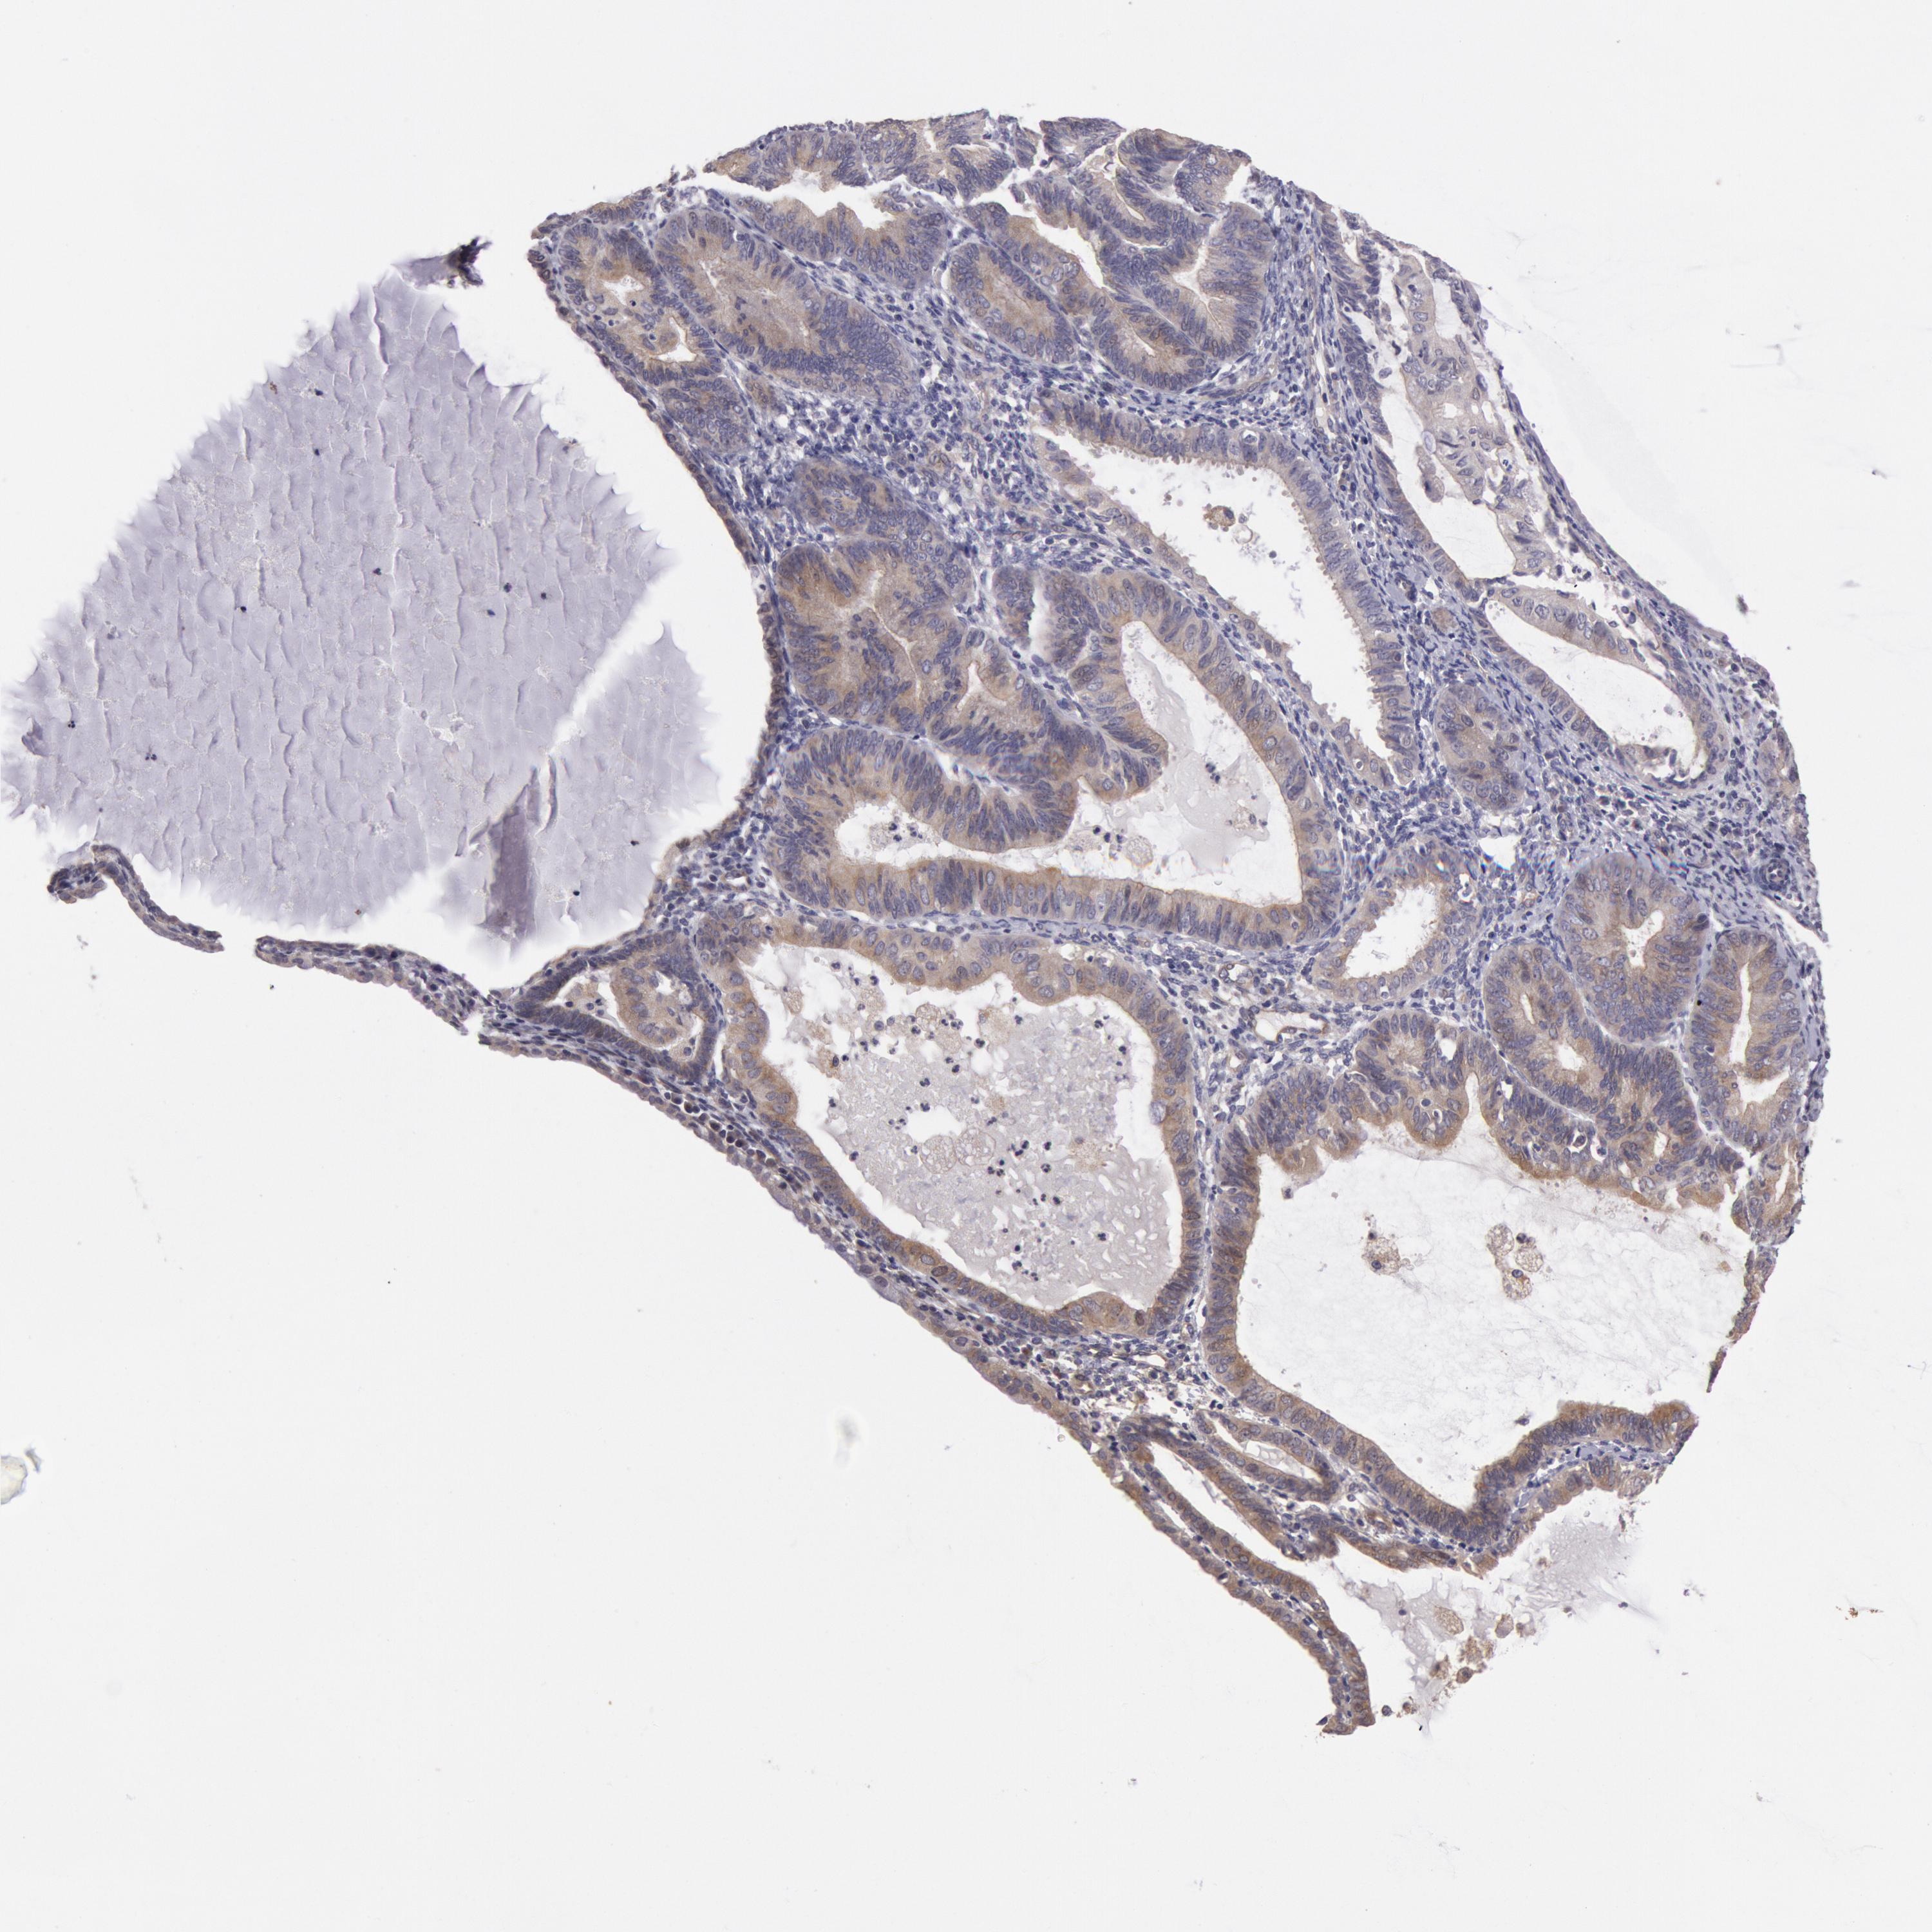

ENDOMETRIAL CANCER - Protein expressioni

A mouse-over function shows sample information and annotation data. Click on an image to view it in a full screen mode. Samples can be filtered based on level of antibody staining by selecting one or several of the following categories: high, medium, low and not detected. The assay and annotation is described here.

Note that samples used for immunohistochemistry by the Human Protein Atlas do not correspond to samples in the TCGA dataset.

Antibody stainingi

Antibody staining in the annotated cell types in the current human tissue is reported as not detected, low, medium, or high, based on conventional immunohistochemistry profiling in selected tissues. This score is based on the combination of the staining intensity and fraction of stained cells.

Each image is clickable and will lead to virtual microscopy that enables deeper exploration of all samples and also displays staining intensity scores, fraction scores and subcellular localization as well as patient and tissue information for each sample.

Antibody HPA001196

Staining

High

Medium

Low

Not detected

Intensity

Strong

Moderate

Weak

Negative

Quantity

>75%

75%-25%

<25%

None

Location

Nuclear

Cytoplasmic/membranous

Cytoplasmic/membranous,nuclear

Adenocarcinoma, NOS